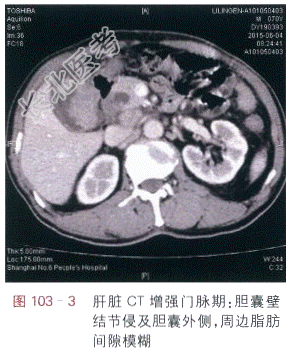

读片分析:肝脏CT平扫:胆囊内见多个结石,胆囊壁内侧呈局限性增厚,形态不规则(见图103-1),肝脏CT增强扫描动脉期:胆囊壁结节呈明显强化,结节呈分叶状,并侵及胆囊壁外侧(见图103-2),门脉期、延时期:胆囊壁结节侵及胆囊外侧,周边脂肪间隙模糊(见图103-3)。